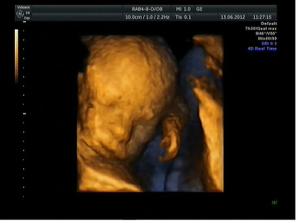

13.6. 3D ultrazvuk - miminko je stydlín, nechtěl nám ukázat hlavičku, pořád si ji schovával 🙂 Odhad váhy dle měření 765 g, 24+5 a předpokládaný termín porodu 28.9.2012, opět potvrzen chlapeček - tentokrát to viděla i maminka s tatínkem 🙂